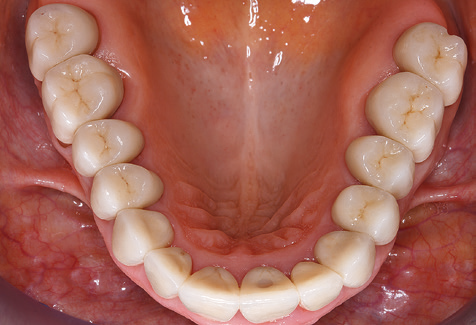

Für den klinischen Langzeiterfolg des parodontal kompromittierten Patienten ist die standardisierte und regelmäßige risikoadaptierte Betreuung im Rahmen der UPT der zentrale Baustein des Behandlungserfolgs. Dies gilt in besonderer Weise für Patienten, die nach erfolgreich abgeschlossener parodontaler Sanierung mit Implantaten versorgt wurden (Abb. 11a und b).